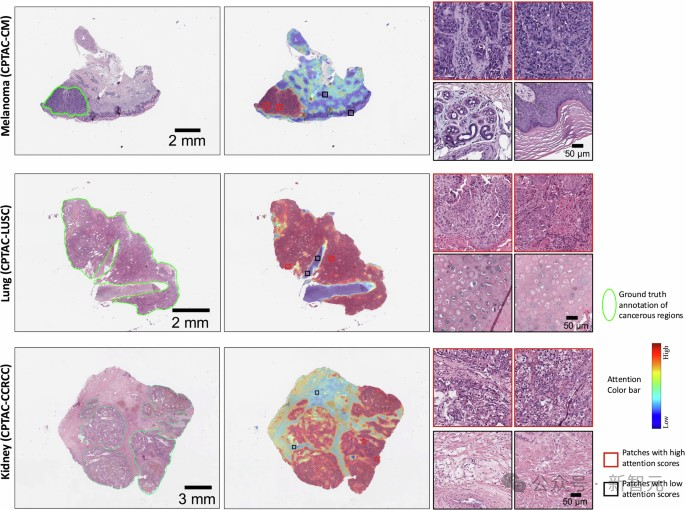

模型注意力得分的可视化显示,CHIEF准确识别了黑色素瘤、肺癌和肾癌的癌变区域

该模型在图像上识别出与肿瘤侵袭性和患者生存率相关的明显模式。

为了可视化特定的区域,CHIEF在图像上生成了热图。当人类病理学家分析这些由AI生成的热点时,他们发现了一些反映癌细胞与周围组织相互作用的有趣信号。

模型注意力的可视化显示了肺癌患者生存预测中的重要区域

其中一个特征是,在长期生存者的肿瘤区域中,免疫细胞的数量比短期生存者更多。Yu指出,这一发现有其合理性,因为更多的免疫细胞可能表明免疫系统已被激活来攻击肿瘤。

在观察短期生存者的肿瘤时,CHIEF识别出了一些需要关注的区域。这些区域的特征包括各种细胞成分的异常大小比例、细胞核上更多的非典型特征、细胞之间较弱的连接,以及肿瘤周围区域中较少的结缔组织。

这些肿瘤周围还有更多的死亡细胞。例如,在乳腺肿瘤中,CHIEF指出组织内的坏死(或细胞死亡)是一个需要关注的区域。另一方面,生存率较高的乳腺癌患者肿瘤周围,更有可能保持类似于健康组织的细胞结构。

研究团队指出,与生存率相关的视觉特征和需要关注的区域因癌症类型而异。